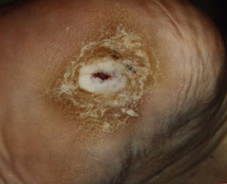

Actual findings at 1999/02/24

Great ulcer with macerating wound edges, stinking wound coating, multiple necrosis.

After extensive debridement and removal of the 6 mm deep necrosis, wound dressing with sterile LIGASANO®white. For decompression of the heel supply with an interrim shoe.